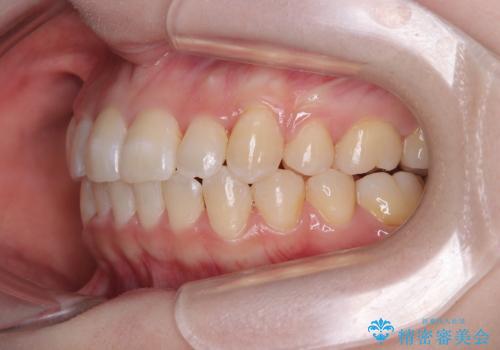

- 八重歯が気になるとのことで来院された患者様です。

上顎前歯部はデコボコが強く、歯を並べるためのスペースが不足しているため、左右の第一小臼歯を抜歯することとしました。

補助装置を併用したおかげで、出っ歯になることなくスムーズに治療を終えることができました。